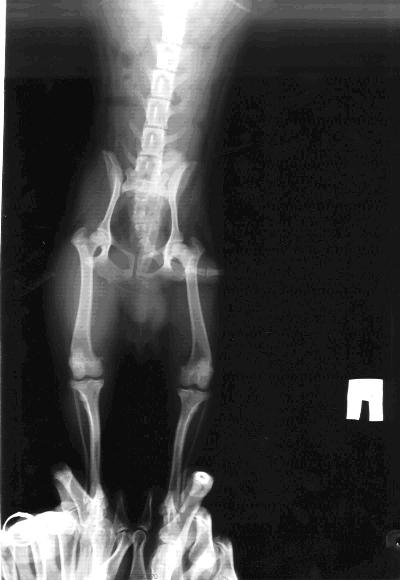

Собачке 9мес, вес - 2, 7кг, натуральный корм; прихрамывает, а иногда и полностью держит на весу заднюю лапку, присутствует атрофированние мышечной ткани задней лапки. Клиническое заключение врача - асептический некроз правой головки бедренной кости. Возможен ли консервативный метод лечения?

Снимок плохого качества, по нему невозможно поставить диагноз.

При болезни Пертеса консервативное лечение неэффективно.